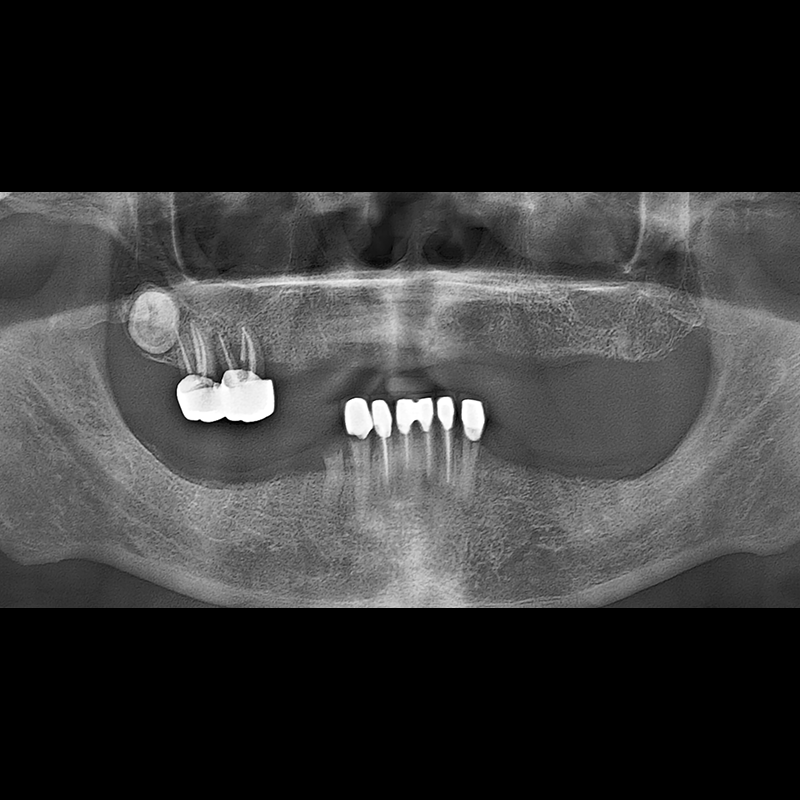

IMPLANT

BEFORE AFTER

임플란트 전후사진 2025.05.30

결손된 치아 부분과 살리기 힘든 치아 위치에 임플란트를 식립하였습니다.